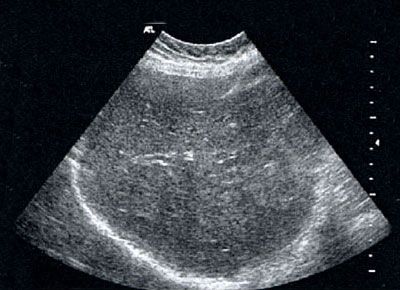

In der Gastroenterologie hat die Ultraschalluntersuchung des Bauchraums (Abdomen-Sonografie) große Bedeutung. Mit ihr lassen sich Organe wie Leber, Gallenwege, Gallenblase, Darm, Bauchspeicheldrüse, Nieren, Milz, Bauchschlagader, Blase, Prostata und Gebärmutter sowie andere Gewebestrukturen sehr genau untersuchen. Dadurch können wir zum Beispiel Erkrankungen wie Gallensteine, Zysten oder Tumoren entdecken und das Krankheitsstadium erfassen. Unser Schwerpunkt wurde von der Deutschen Gesellschaft für Ultraschall in der Medizin (DEGUM) als qualifizierte Weiterbildungsstätte zertifiziert.